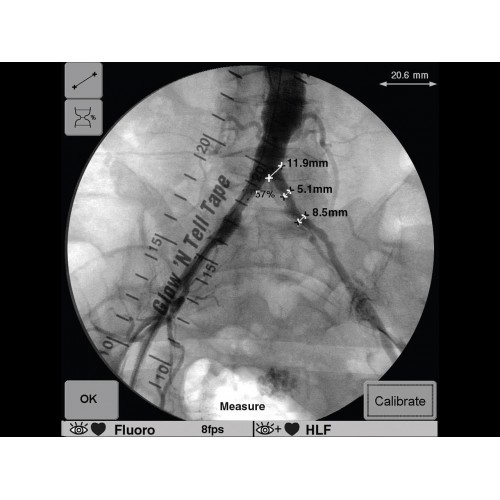

GE OEC 9900 Elite оснащен революционной системой визуализации, обеспечивающей кристально четкое изображение анатомических структур. Интеллектуальная система автоматически адаптирует параметры исследования под конкретную хирургическую задачу, обеспечивая оптимальный баланс между качеством изображения и лучевой нагрузкой. Особое внимание уделено удобству работы операционной бригады.

В операционной практике GE OEC 9900 Elite демонстрирует исключительную эффективность при проведении сложных малоинвазивных процедур. Оборудование позволяет значительно сократить время вмешательства и повысить его безопасность для пациента. Многие хирурги отмечают улучшение точности операций и комфорт работы с системой.

В ведущих медицинских центрах GE OEC 9900 Elite успешно применяется для проведения сложных кардиологических, нейрохирургических и ортопедических вмешательств. Система доказала свою эффективность при выполнении стентирования коронарных артерий, эмболизации сосудов головного мозга и вертебропластики. Многие учреждения отмечают повышение качества операций после внедрения этого оборудования.